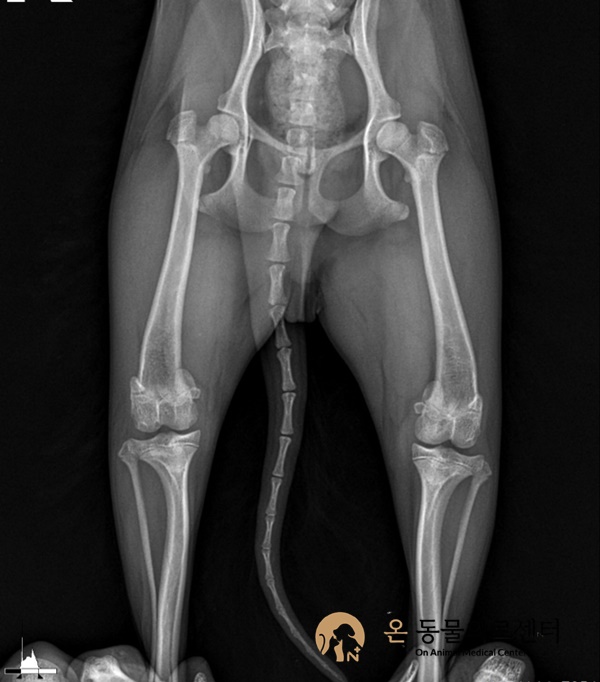

발등뼈 골절

수술 전

수술 후